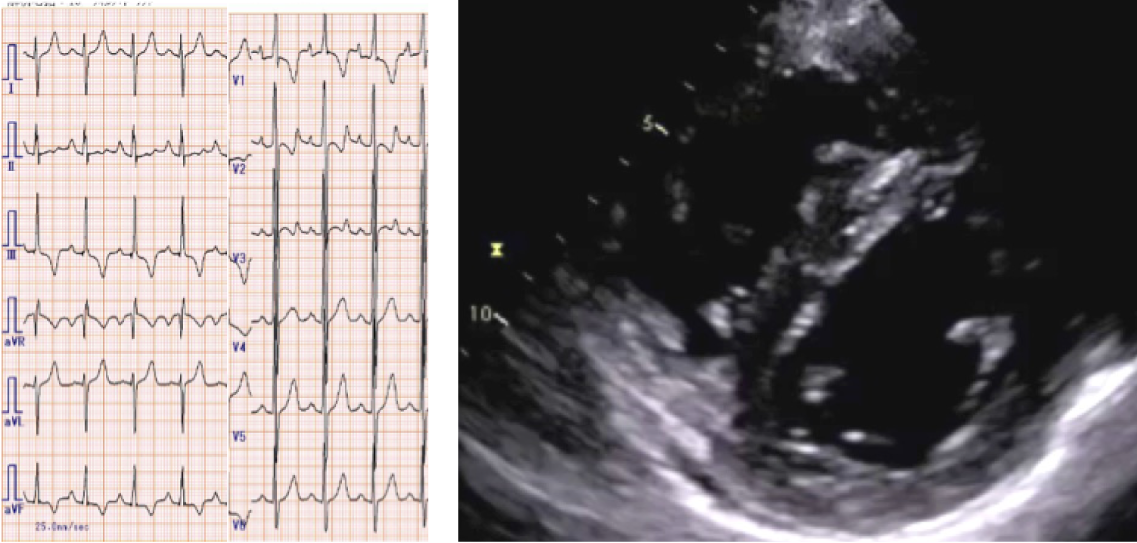

症例2:図1 12誘導心電図、図2 心エコー所見

出典

症例2:図5 肺動脈バルーン形成術(BPA)施行前後